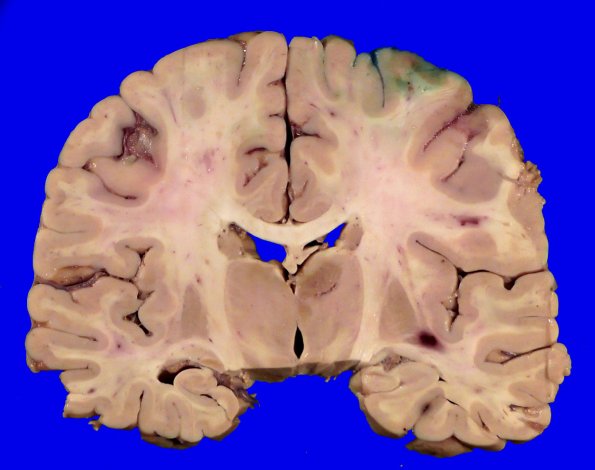

At autopsy the unfixed brain weighed 1200g. ---- 18B1,2 Scattered lesions visible in the white matter and as a large focus in the right thalamus are necrotic and occasionally hemorrhagic.